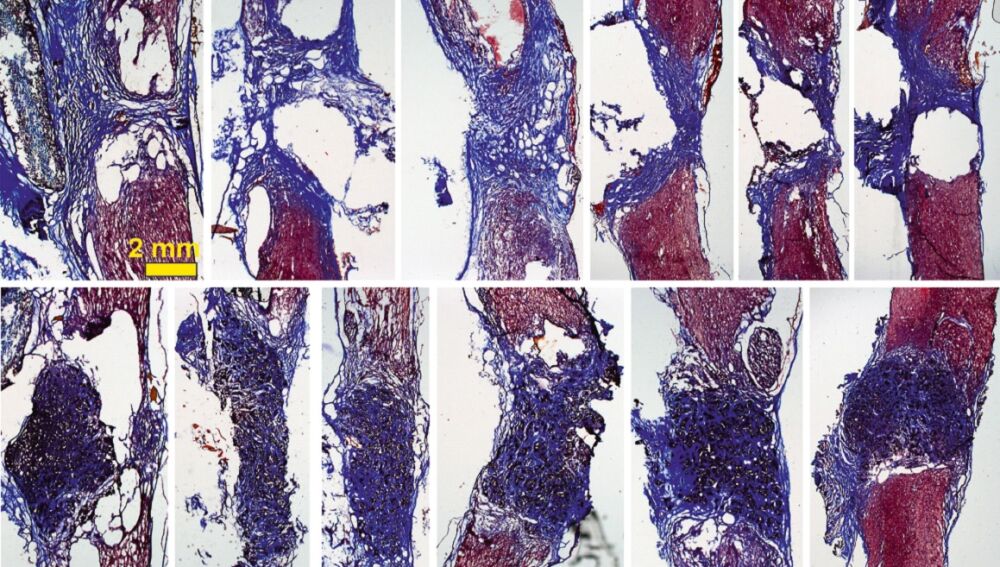

Los tejidos ‘colonizan’ el espacio hueco Sinc

De esta manera, cuando se coloca el scaffold en la médula espinal –en este caso en un modelo de rata con la médula espinal completamente seccionada a nivel torácico–, "vemos que aparecen gran cantidad de vasos sanguíneos, que son fundamentales para nutrir el nuevo tejido, y neuritas (los filamentos que unen unas neuronas con otras)".

La investigadora explica que con esto se observa “cómo las neuronas que han sobrevivido en la zona alrededor de la lesión proyectan sus prolongaciones a través del scaffold y lo invaden en toda su extensión 3D". Todo esto, además, mejora con el tiempo: los resultados son incipientes tras 10 días de implante, pero son mucho más prometedores a los 4 meses.

"Nuestros scaffolds de óxido de grafeno reducido favorecen el crecimiento de vasos sanguíneos más abundantes y más grandes, y neuritas más abundantes, más largas y, además, distribuidas de manera más homogénea en el espacio de la lesión", destaca Serrano.